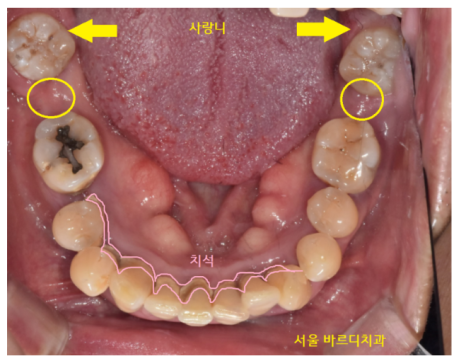

230612

환자분처럼 양쪽 어금니가 다 없고

임플란트 뼈이식을 많이 해야할경우

안전하게 오른쪽 왼쪽 나눠서

임플란트 수술을 진행합니다.

환자분은 왼쪽이 많이 불편하시다 하셔서

왼쪽부터 수술을 진행하였습니다.

(환자분의 요구사항이 1순위 반영사항입니다)